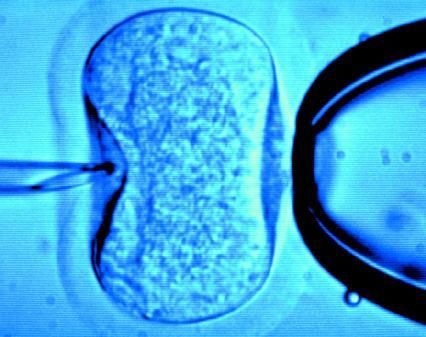

據(jù)英國《每日郵報》1月18日報道,英國一位60歲老婦將成為英國接受試管受精最年長者。這位老婦名叫蘇珊·托勒夫森,是一位退休教師,到今年10月她就滿60歲了。2008年,蘇珊曾去俄羅斯接受試管受精,在英國生下了她的第一個孩子。

倫敦哈利街的私人診所是英國試管嬰兒手術成功率較高的醫(yī)院之一,醫(yī)生們在上周一同意幫助蘇珊·托勒夫森進行第二次人工受孕。通常情況下,私人診所只在特殊情況下給50歲以上的婦女進行試管受精,例如,患者仍然有月經(jīng)周期。這件事引起了絕經(jīng)后婦女是否有生育權利的倫理大討論,現(xiàn)在要求提高生育治療年齡上限的呼聲越來越高。

現(xiàn)在,蘇珊·托勒夫森一家人很幸福,丈夫尼克·邁耶是一位公司經(jīng)理,比她小11歲,他們的女兒今年2歲。專家表示,蘇珊很健康,她的女兒如果能有一個兄弟姐妹會更好,于是蘇珊想再次接受試管受精!缎瞧谌锗]報》獲悉,倫敦哈利街私人婦女診所的高級工作人員已經(jīng)同意為蘇珊做試管受精,還決定幫助另一位57歲的老婦受孕。(海瀾)